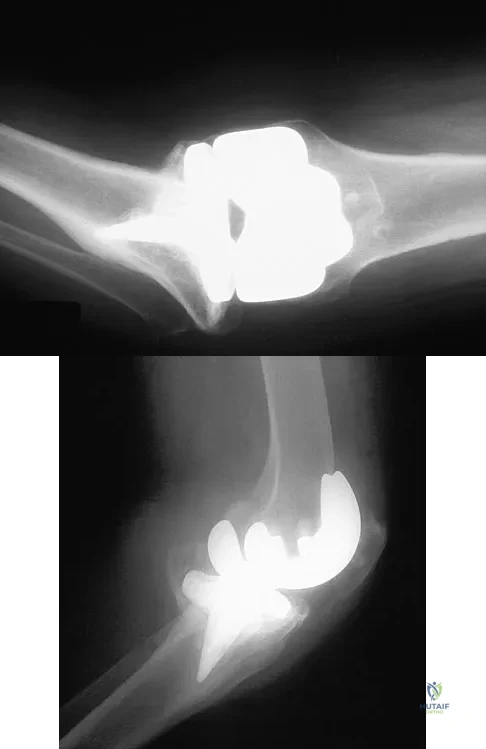

A 38-year-old woman who tripped and fell on her outstretched arm reports pain with movement. Examination reveals swelling. AP and lateral radiographs are shown in Figures 43a and 43b. Management should consist of

Figure 27 shows the radiograph of a 26-year-old man who sustained a closed head injury and a closed elbow dislocation 6 weeks ago. Examination reveals 65 degrees to 115 degrees of flexion, and intensive physical therapy has resulted in no improvement. A decision regarding the timing of surgical correction of the contracture should be based on